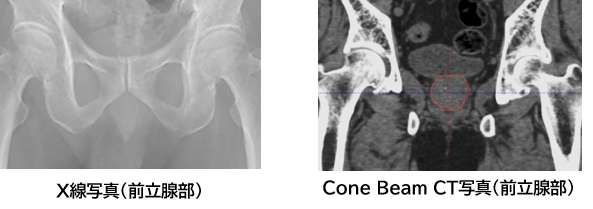

当院の放射線治療装置は、Varian社製 TrueBeam(HyperSight搭載) です。高精度に放射線照射を行うため、少ない線量でコーンビームCT(CBCT)を撮像し、放射線画像による位置照合を行っています。導入したリニアックには HyperSight(ハイパーサイト)イメージングシステム を搭載しており、従来よりも短縮された撮影時間で照合用のCT画像を取得できるため、より短時間で効率よく位置合わせを行うことが可能です。